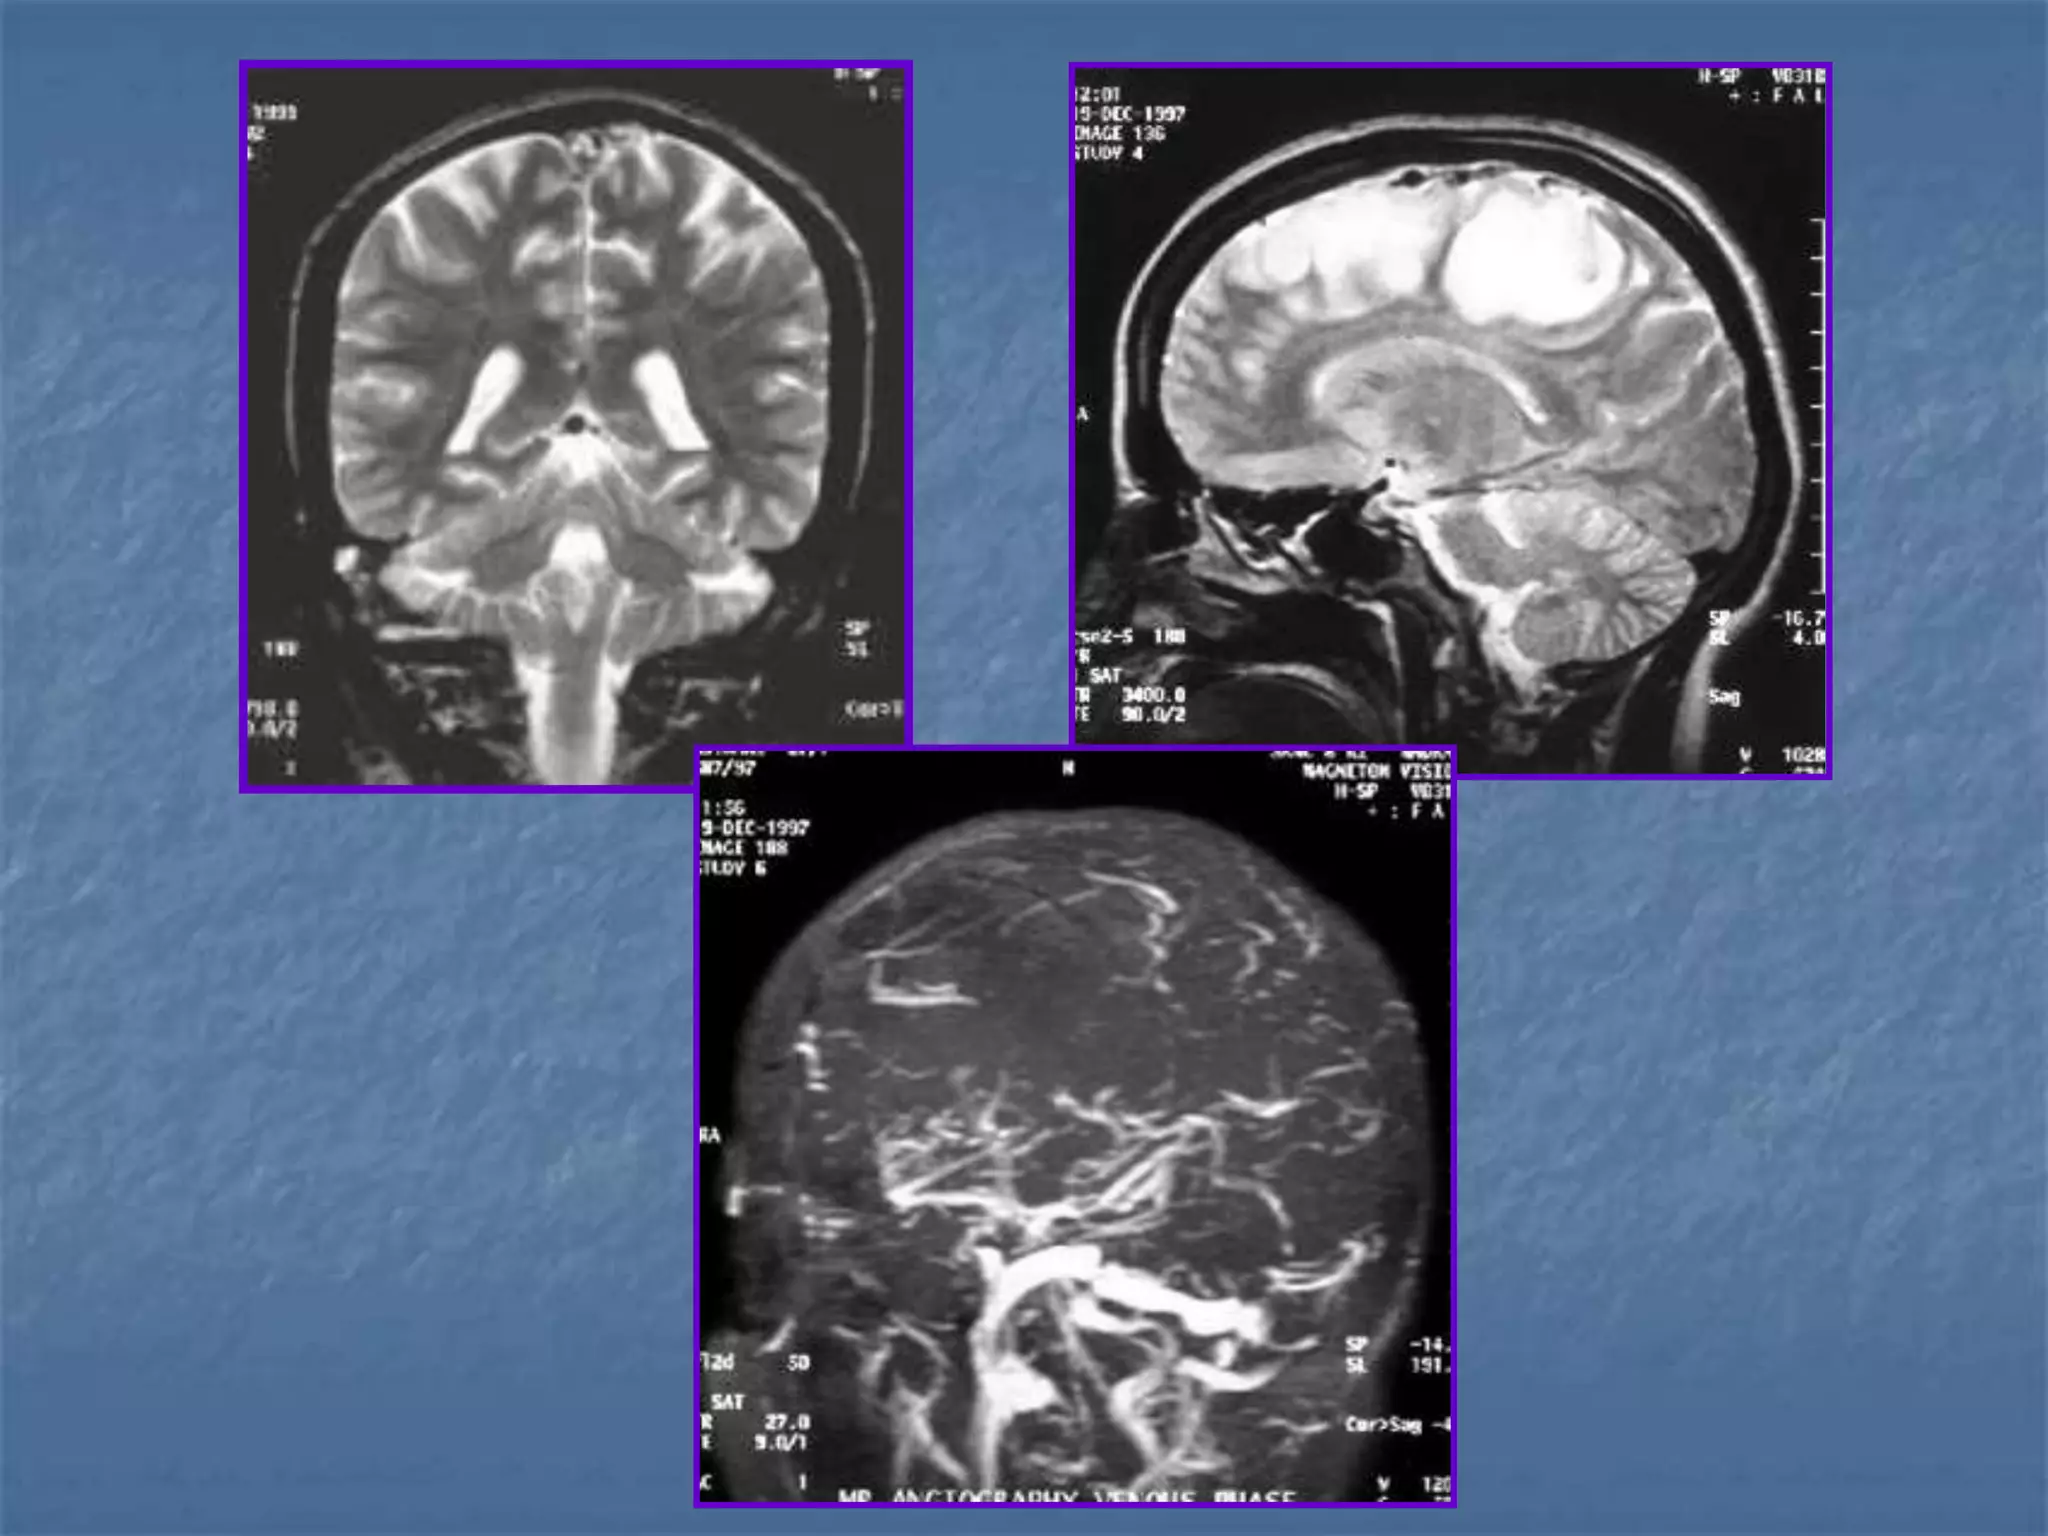

Venous Sinus Thrombosis with Venous

Infarct

 Clinical symptoms – head ache, seizures

 Pathology is due to decrease in perfusion pressure as

the venous pressures elevate due to occlusion.

 Predisposing conditions are dehydration, infection,

polycythemia, sickle cell disease, hypercoagulable

states, peripartum, OCP poisoning.

Imaging findings

 Unilateral / bilateral parenchymal hypodensities

 Not limited to an arterial territory

 May be associated with hemorrhage

 Signs: Delta sign, Enhancement of walls of sinus than

their contents.